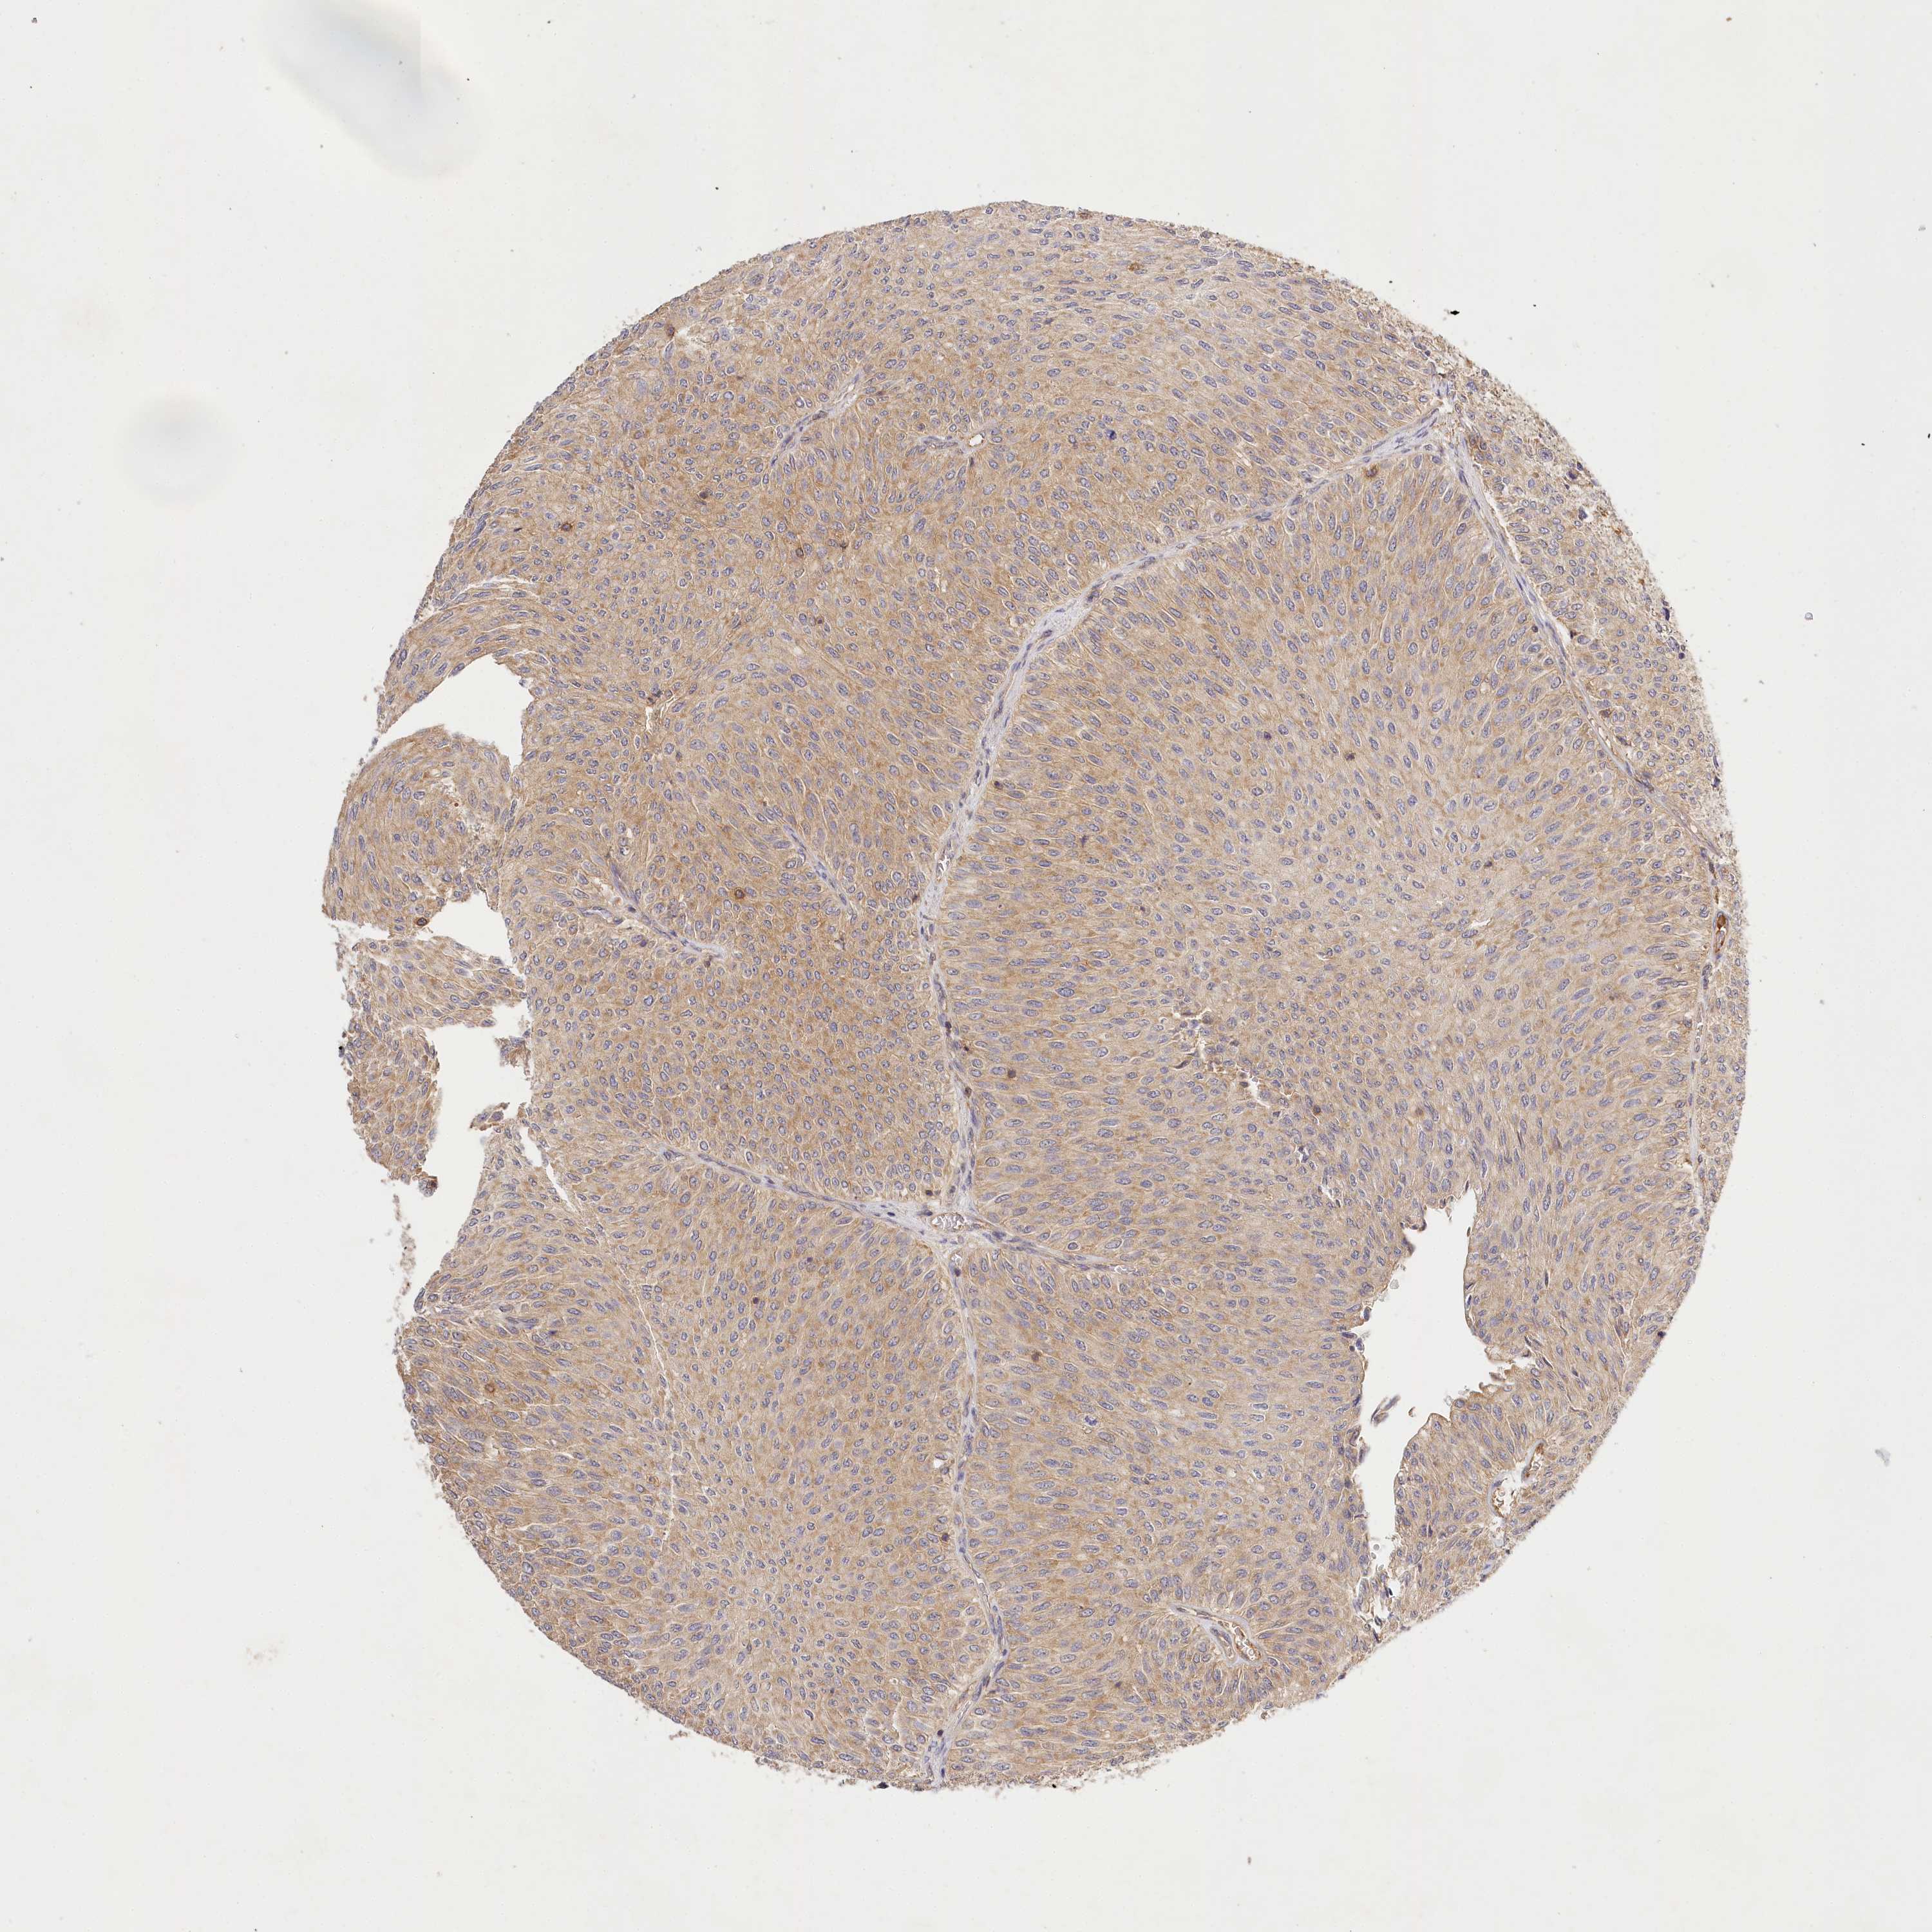

UROTHELIAL CANCER - Protein expressioni

A mouse-over function shows sample information and annotation data. Click on an image to view it in a full screen mode. Samples can be filtered based on level of antibody staining by selecting one or several of the following categories: high, medium, low and not detected. The assay and annotation is described here.

Antibody stainingi

Antibody staining in the annotated cell types in the current human tissue is reported as not detected, low, medium, or high, based on conventional immunohistochemistry profiling in selected tissues. This score is based on the combination of the staining intensity and fraction of stained cells.

Each image is clickable and will lead to virtual microscopy that enables deeper exploration of all samples and also displays staining intensity scores, fraction scores and subcellular localization as well as patient and tissue information for each sample.

Antibody HPA032060

Antibody HPA032062

Antibody CAB034116

Staining

High

Medium

Low

Not detected

Intensity

Strong

Moderate

Weak

Negative

Quantity

>75%

75%-25%

<25%

None

Location

Nuclear

Cytoplasmic/membranous

Cytoplasmic/membranous,nuclear

Urothelial carcinoma, Low grade

Urothelial carcinoma, High grade